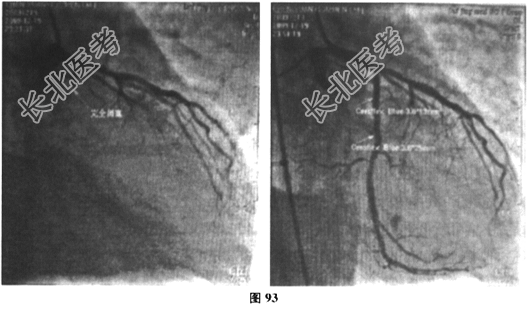

- 多项选择题3.[提示]患者入院后予以急诊冠脉介入治疗,术中见冠脉分布呈右优势型, LM末端狭窄10%~20%,LAD近中段狭窄30%, D1段狭窄70%,LCX近段完全闭塞, 管腔内可见血栓影,RCA近中段长病变大于20mm, 狭窄最重处约50%(图92、图93),予以p-LCX植入支架2枚, 术后患者胸闷症状缓解,但术后患者间断低热, 体温最高38.2℃,伴右侧颞部搏动性痛伴头胀, 余无其他不适,监测血沉85mm/1小时末, CRP38.3mg/L。